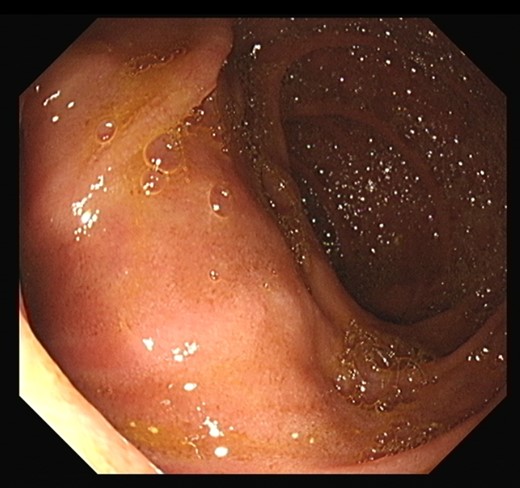

The patient underwent an MRCP which demonstrated mild distension of the gallbladder with several calculi. There was intra- and extra-hepatic biliary dilatation to the level of the ampulla. A very large fluid and air filled periampullary duodenal diverticulum measuring ~8 cm in the long axis was also noted (Figs 1–3). This finding was unchanged compared to a CT study from 6 months previously. The CBD was dilated to the level of this diverticulum and the cause of the patient’s biliary dilatation and obstruction. Interestingly, an unusual appearance to the kidneys was recorded with multiple microcystic changes in both kidneys, which is typically reported in patients with lithium induced renal disease. A gastroduodenoscopy revealed a large periduodenal diverticulum in D2 (Fig. 4).

DISCUSSION